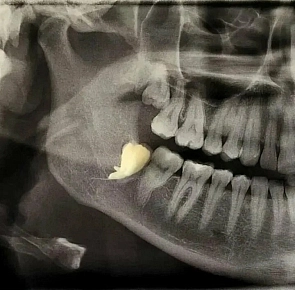

Что происходит, если отсутствует хотя бы один зуб?